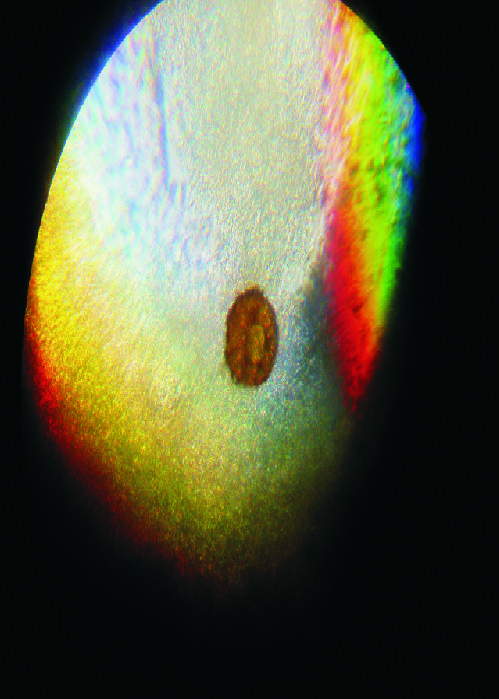

znalezione w odchodach - powiekszenie x120 i x500

(jest okragle, tylko na tych zdjeciach robi sie jajo)

Teraz o tym co (słabo

) widać. Na nr.1 to może być skorupka pełzaka - ameby. Na drugim - nie wiem (wydaje mi się zbyt symetryczny ten obiekt, żeby mógł być czymś, co nas może interesować

). Teoretycznie mógłby być niby jakąś cystą, niekoniecznie groźną, ale moim zdaniem jest zbyt symetryczny.

to sa fotki tego samego ustrojstwa w powiekszeniach x120 i x500,